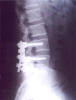

IP Artrodesis por lumboartrosis y laminectomía